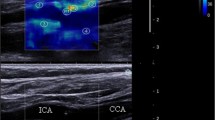

SWE image analysis

The SWE scans were analyzed retrospectively, and arterial wall YM was quantified using the Aixplorer’s in-built analysis software for 2 mm ROIs. ROIs were placed in different CCA locations to assess the variability of YM measurements with ROI position as shown in Fig. 5. The locations include anterior, posterior, left, right, distal, and proximal. Criteria for inclusion of measurements in further statistical analysis were as follows: (1) good image acquisition; (2) complete filling of the shear wave elastogram; and (3) adequate cine-loops. Exclusion criteria included are as follows: (1) poor image acquisition; (2) insufficient shear wave elastogram filling; and (3) cine-loops with less than five SWE frames.

SWE technology has been used in many applications, but its suitability for vascular applications remains hotly debated. It has been proposed that SWE might have potential clinical value in the diagnosis of vascular disease, and in particular, detection of early changes in arterial vessel elasticity [19]. However, concerns have arisen over the reliability of SWE YM estimates and the potential impact of factors such as ROI size and position on YM estimates. Ultimately, if measurement variability is greater than typical clinically significant differences, this will limit the usefulness of SWE in clinical practice. This study focused on the identification and quantification of sources of variability in arterial wall SWE measurements (Fig. 5).

There was no significant difference between YM measurements between the left and right CCA, with a bias of 0.6 in the anterior wall (mean 59 ± 25 kPa) and a bias of 1.4 between the left and right posterior walls (mean 52 ± 26 kPa). The high variability between these YM measurements (95% limits of agreement from -28 to 41 kPa) shows that measurement variability is far higher than the bias. Differences in results between ROIs may be attributed to an artifact of the SWE technique related to the shear wave propagation or implementation in the scanner, depth of the ROI, or the position of the ROI within the anterior wall where the surrounding tissues including muscles may be of high YM. A real difference due to different tethering between anterior and posterior walls would also explain the findings and requires further investigation. Preliminary, unpublished data from our vessel phantom models surrounded by water or a tissue mimic highlighted the importance of the surrounding medium, supporting this observation. It showed that in a submerged phantom YM anterior wall measurements were significantly higher than posterior wall. Moreover, results from our phantom test object specifically clarify this aspect in which YM measurements decrease with increasing depth, and the maximum penetration depth was dependent on the pipe diameter [26]